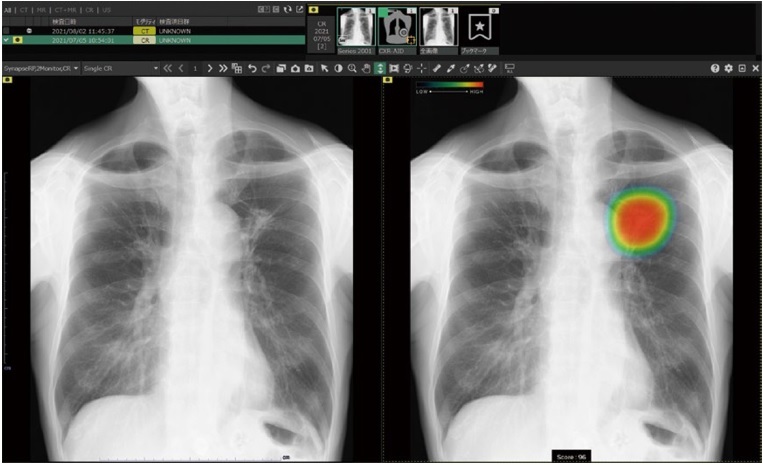

胸部X線画像を自動解析。病変の存在が疑われる領域を検出・マーキングし、見落し防止を支援。